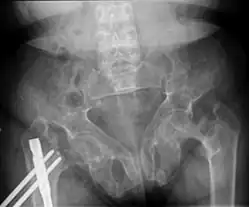

Brown tumors in the pelvis and a hip fracture.[18] -